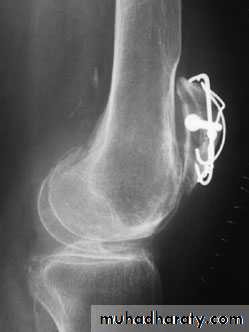

Continuous pull of the fragments by a muscle as in avulsion fr of patella or olecranon.

Traction for disimpaction

Revers the direction of troma for reductionPOP cast